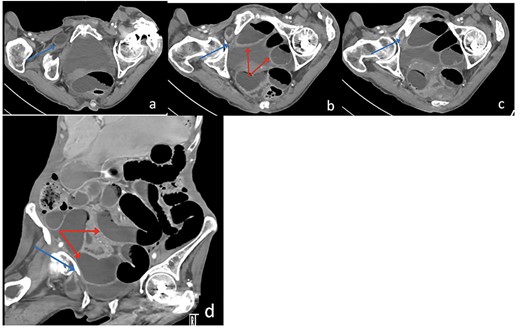

Due to the high-grade small bowel obstruction, the patient was pushed as an emergency case to the operating room. The surgery started and ended as a laparoscopic procedure with three small incisions; 12, 11 and 5 mm port sizes located supraumbilically, right and left midclavicular line relatively. Once the peritoneum was penetrated, and gas insufflated, diagnostic laparoscopy was done, and the obturator hernia with bowel content was visualized (Fig. 3), with a transitional zone at the hernia site showing a proximal dilatation and distal collapse of the small bowel. After that, reduction of the hernia content was subsequently made with no signs of gangrene or ischemia of the bowel. Then, the small bowel was run as a whole to eliminate any other transitional zones or pathology, which was unremarkable. Therefore, as there was no contamination, ischemia or perforation, a Vicryl mesh was elected and inserted as a plug into the obturator opening using a peritoneal flap and fixed (Fig. 4). Once the fixation was obtained, a ProGrip mesh was then applied to cover the whole right area (Fig. 5), which was covered by the peritoneum afterwards. The abdomen was inspected and the bowel looked healthy. Lastly, the ports were removed, the incisions were closed, the skin was clipped and then the dressing was applied.

An intraoperative figure of the obturator hernia transitional zone revealing the hernial sac and protruded bowel segment.